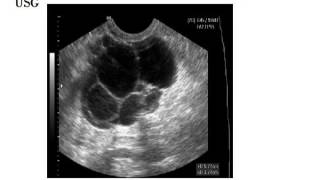

Cara kerja alat USG

Cara kerja USG abdomen

Cara membaca hasil USG abdomen

Cara pemeriksaan USG abdomen

Gambaran USG abdomen normal

Arti USG whole abdomen

Cara membaca USG abdomen

Apa itu USG whole abdomen